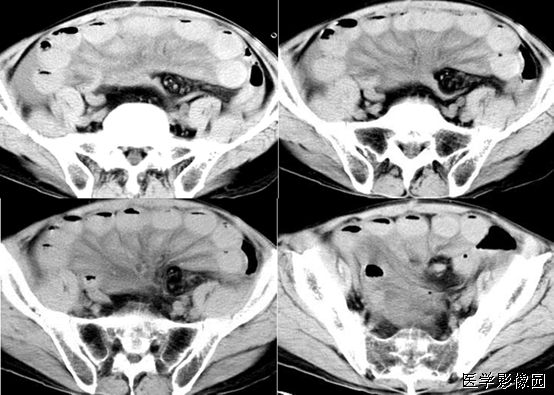

13、三明治征(夹心面包征或夹心饼征)

指2个均质软组织肿物组成三明治面包,系膜脂肪和管状物为构成夹心,是腹部CT横断扫描时的影像表现。系膜脂肪和血管组成夹心,肿大淋巴结组成面包;在给予增强剂后系膜管状结构(血管、肠管)相对脂肪增强,夹心层突出。因为淋巴结增大会压迫血管,阻碍静脉回流,使夹心层内增强的血管更加明显。

当经静脉及口服造影剂后,肠系膜血管结构较脂肪明显强化,从而可使夹心更加突出。导致肠系膜淋巴结肿大的病因很多。除淋巴瘤外,癌、肉瘤、类癌、获得性免疫缺陷相关性淋巴结增生综合征、结核、肠源性脂肪代谢碍及炎症性肠病等也是最常的病因。

癌、肉瘤及类痛均可起源于小肠,然后向肠系膜淋巴结扩散。这些肿瘤快速侵犯肠壁而导致穿孔、出血及弥漫性病变。感染性及炎性病变通常不会引起巨大的块状淋巴结肿大,它们所引起的淋巴结肿大,,周边可见环形强化,此点与结核相似。因此这些肿瘤,感染及炎性病变不会产生三明治征。

三明治征为肠系膜淋巴瘤的特异征象。因为只有在肠系膜淋巴瘤中淋巴结才可以长得很大,并包绕脂肪、肠管和血管而不产生任何临床症状。肠系膜淋巴瘤偶尔可侵犯浆膜及固有肌层,有时会引起小肠出血但极少引起游离性穿孔。肠系膜淋巴瘤还可以引起腹膜后淋巴结肿大。

绝大多数肠系膜淋巴瘤是非霍奇金淋巴瘤。过去在临床上通常难以确定非霍奇金淋巴瘤是否累及肠系膜。随着现代影像技术的发展及影像检查的普及.非霍奇金淋巴瘤累及肠系膜及其所表现的三明治征经常可以见到。

患者的免疫功能紊乱是非霍奇金淋巴瘤的危险因素。例如.AIDS患者易于并发非霍奇金淋巴瘤,这与AIDS相关性淋巴结增生综合征有本质的区别。随着实质器官移植及骨髓移植的增多,移植后淋巴组织增生性疾病有增多趋势。淋巴组织增生性疾病为EB病毒驱动的B细胞增殖性病变,在形态学上淋巴组织增生性疾病与侵袭性非霍奇金淋巴瘤难以区别,但由于发病机制及临床处置均不相同.因此,可将淋巴组织增生性疾病看作一种独立的淋巴增生性疾病。淋巴组织增生性疾病通常累及胃肠道.但不引起浅表结节样的改变。对于行器官移植的患者,如果断层影像显示夹心面包征,必须考虑到存在淋巴组织增生性疾病的可能性。

总之,三明治征指的是CT柏横断面上,巨大增生的肠系膜淋巴结包绕肠系膜脂肪和血管而形成的类似三明治的影像。对于设有移植病史的患者,非霍奇金淋巴瘤是三明治征的主要病因;有移植病史的患者,产生三明治征的原因则可能是淋巴组织增生性疾病,随着接受移植手术的患者不断增多,三明治征可能会在临床上越来越常见。

下图是一个恶性肿瘤腹膜后淋巴结转移患者:

下边两幅图更典型:

图1:非何杰金淋巴瘤患者口服造影剂后增强CT横断面。显示2个巨大系膜淋巴肿物(2个面包-带尾箭头),包绕中心系膜和增强的血管。注意增强的小肠位于周边,腹膜后淋巴结显著增生-箭头)。

图2:患者6个月前曾行左肾移植发现PTLD,血管和口服造影剂横断CT显示三明治征——系膜淋巴肿物(实心带尾箭头),靠近右肾(箭头),有腹膜淋巴结肿大(空心带尾箭头)。